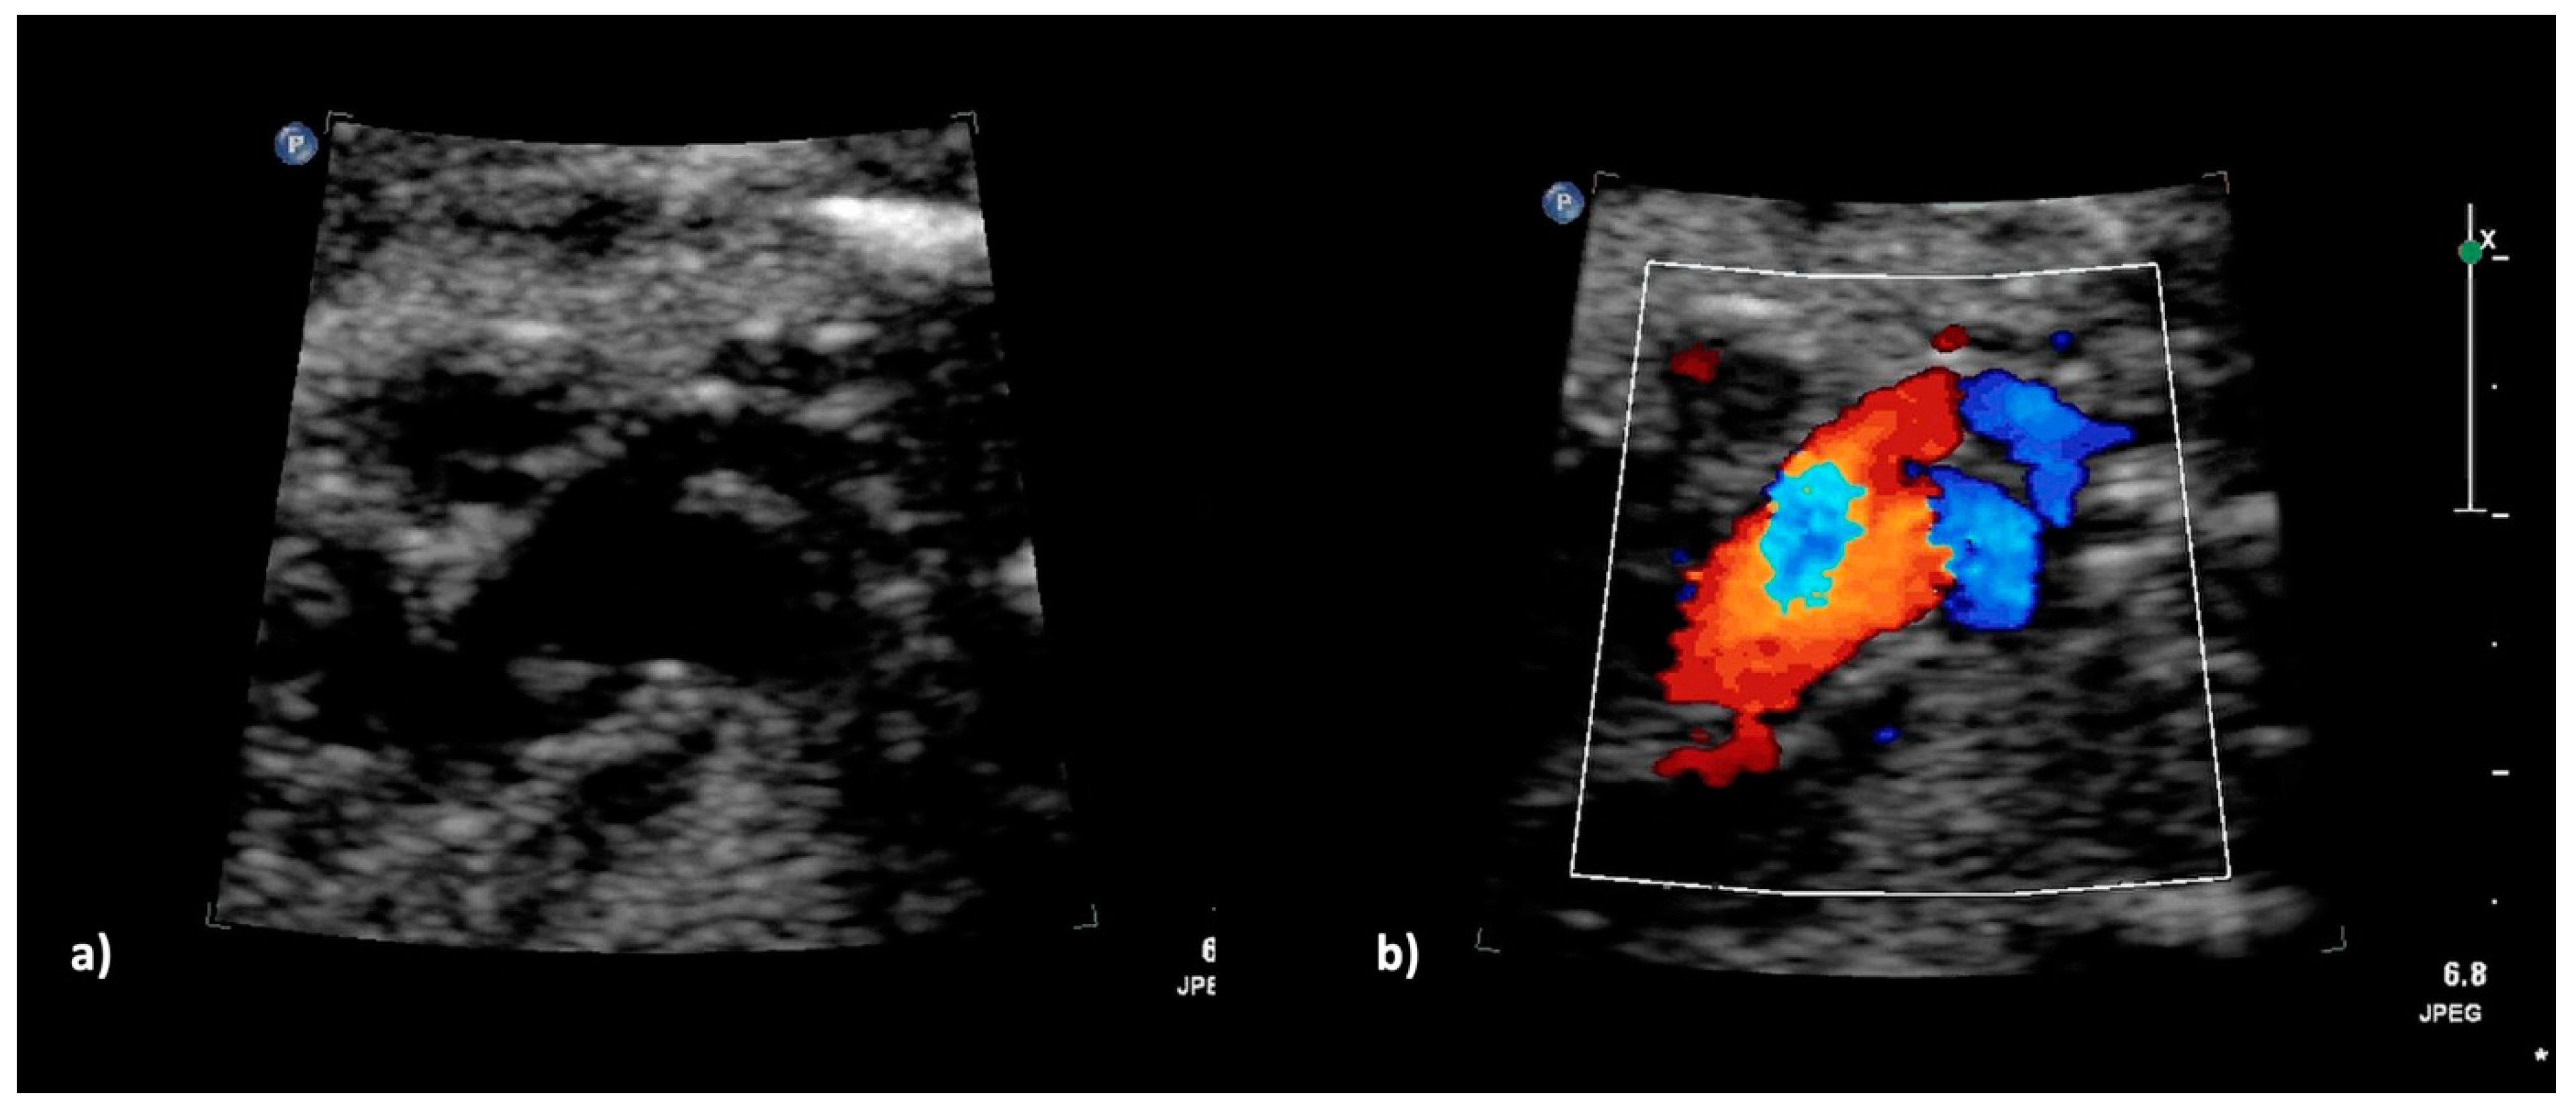

Figure 3.

(a,b): Truncus arteriosus type 4 with interrupted aortic arch type b at 23 + 5 weeks. (a) The 2DE shows the ventricular outlet part with the overriding common trunk, the truncal valve as well as the wide truncus pulmonalis and the hypoplastic ascending aorta (pulmonary dominance); (b) The color Doppler mode shows the outflow from both ventricles into the common arterial trunk and further into the pulmonary trunk as well as into the hypoplastic aorta.